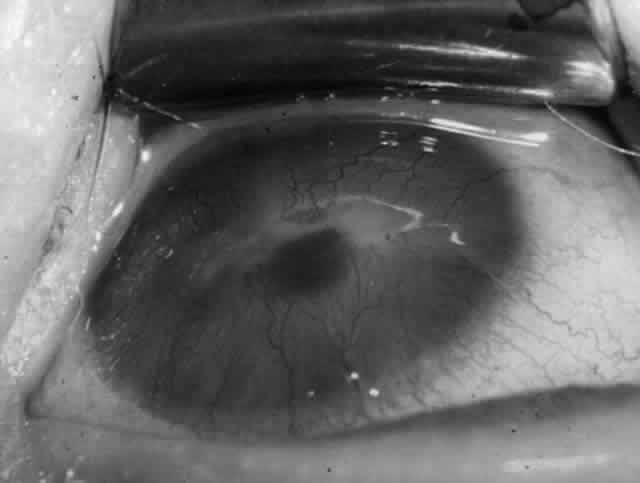

Clinically, the ocular disease in cicatricial pemphigoid (OCP) may present unilaterally in the form of a chronic, recurrent catarrhal conjunctivitis, but it eventually becomes bilateral. Subepithelial fibrosis is characteristic of stage 1 of OCP (Fig. 7). Stage 2 shows fornix foreshortening (Fig. 8), and symblepharon formation is the hallmark of stage 3 (Fig. 9). Stage 4, end-stage disease, is characterized by ankyloblepharon and surface keratinization (Fig. 10). Obstruction of the lacrimal ductules and meibomian gland ducts eventually produces an unstable tear film and progressive sicca syndrome, but it is to be emphasized that OCP is not a dry-eye syndrome until late in the disease course.20 Trichiasis and entropion occur because of the subepithelial fibrosis, with eventual keratopathy, corneal neovascularization, and corneal ulceration and scarring.20

Fig. 7. Stage 1 cicatricial pemphigoid, with cicatrizing conjunctivitis, and fine striae-type areas of subepithelial fibrosis, but without evidence of shrinkage of the conjunctiva.

Fig. 8. Stage 2 cicatricial pemphigoid, with fornix foreshortening and subepithelial fibrosis without frank symblepharon formation.

Fig. 9. Stage 3 of an eye affected by cicatricial pemphigoid. The conjunctival “shrinkage” continued and a frank symblepharon developed.

Fig. 10. Stage 4 cicatricial pemphigoid. Progressive shrinkage of the conjunctiva resulted in extreme trichiasis and distichiasis and keratopathy, with compromise of meibomian ductules and lacrimal ductules and the production of a totally dry eye.